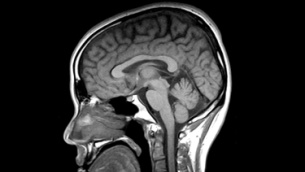

L’IRM le plus puissant du monde dévoile ses premières images